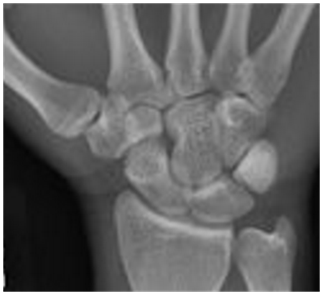

Plain x-rays remain the gold standard for diagnosis and classification of CMCJ dislocation.5 A postero-anterior (Figure 2), oblique and lateral view series is often adequate to make the diagnosis. In unclear situations other further views or specialist imaging may be warranted. A systematic examination of the whole radiograph is mandatory to pick these injuries.14

Figure 2 PA radiographs of the hand.

Parallelism

For the 2nd through 5th carpometacarpal articular surfaces, opposing surfaces on the metacarpal base and the corresponding carpal bones are parallel. Comparing the space between the carpal bones and the metacarpal bases to a capital M, or “M line” helps to identify any anomalies.14

Symmetry

The width of the 2nd through the 5th carpometacarpal joint spaces is uniform, measuring 1-2mm. Disappearance of the CMC joint space suggest dislocation14 (Figure 3).